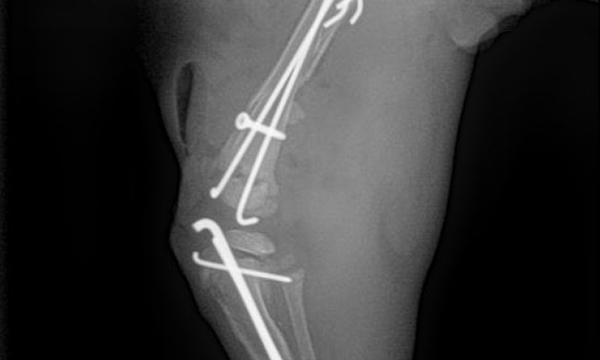

수술케이스 ④ 블*강아지 - 경골 복합골절

수술케이스 4 before BEFORE

수술케이스 4 after AFTER